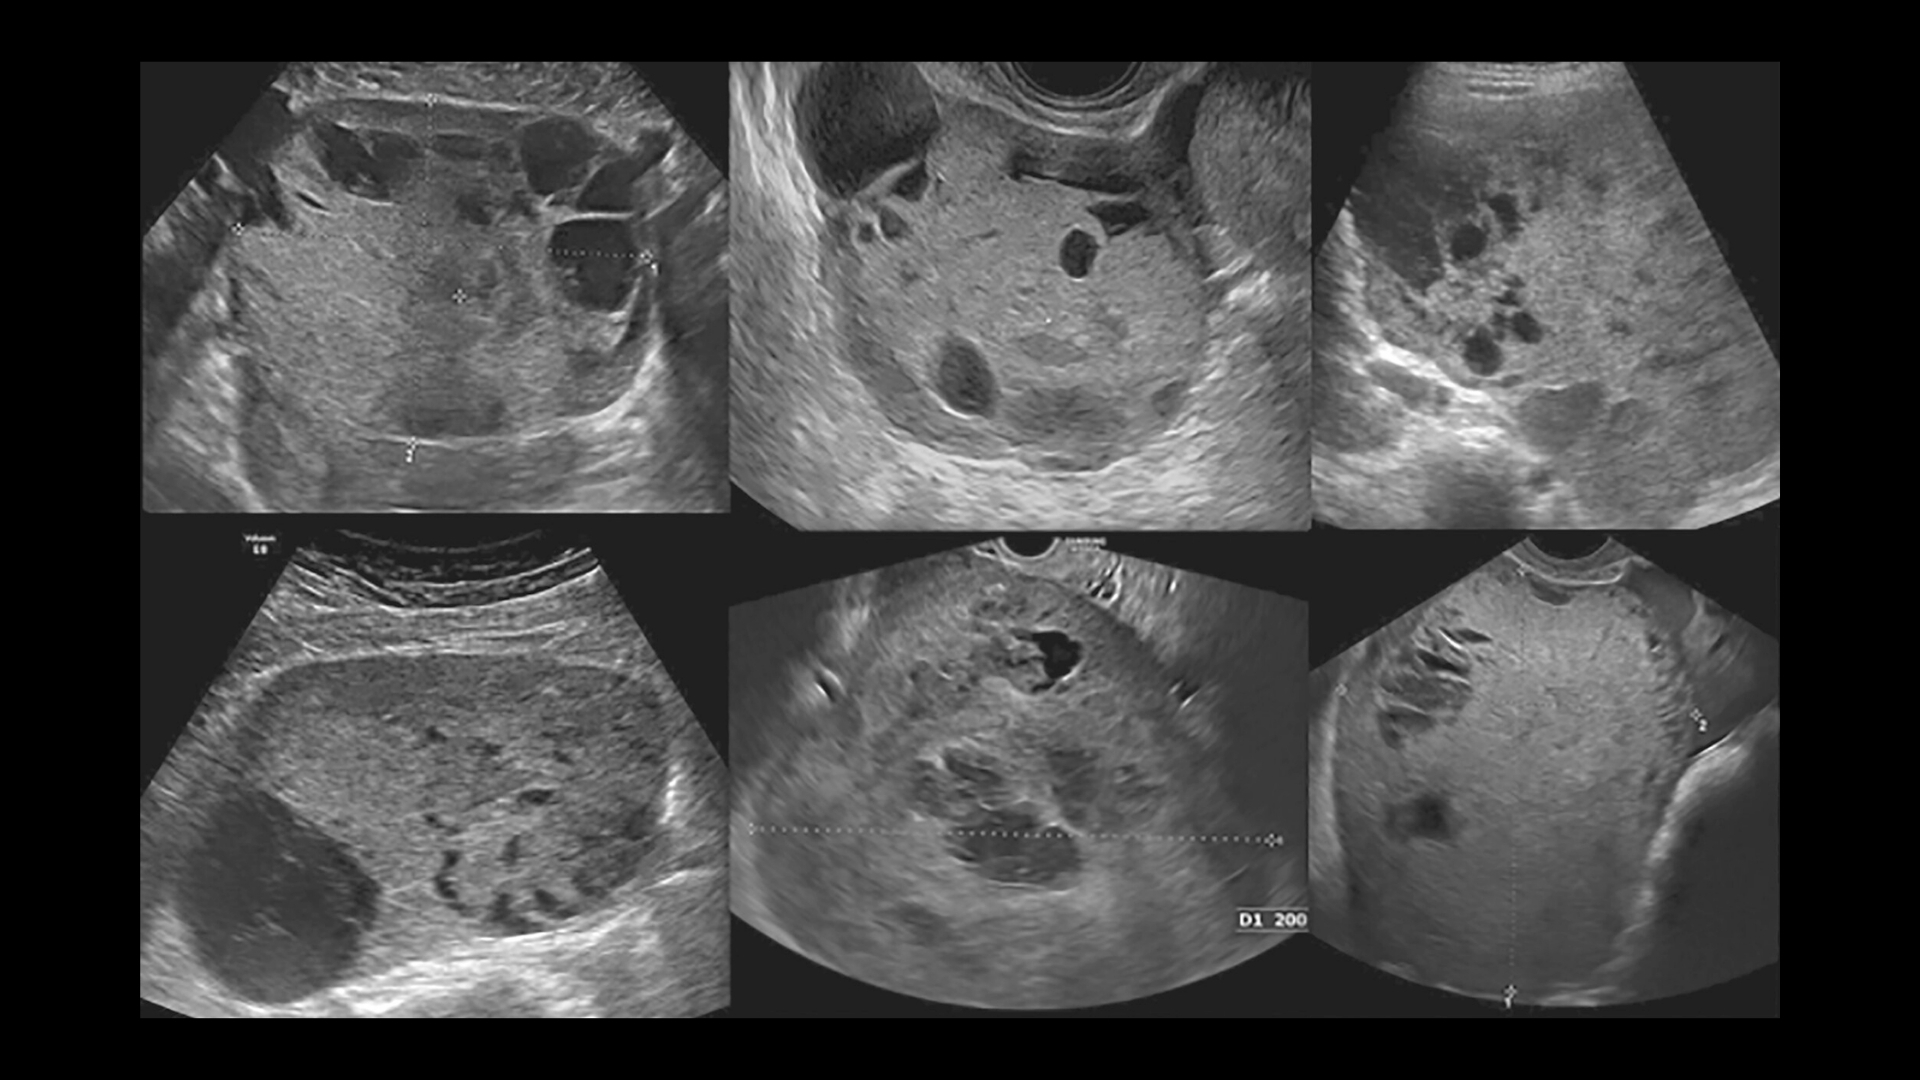

• 影像和活檢可提供確切證據,以進行精確的分期和治療規劃

在診斷時確定腫瘤的分期對卵黃囊腫瘤患者的存活率有關鍵性的影響。準確的分期可提供量身訂做的介入治療,提升療效並大幅改善存活機率。

• 病變通常較小,直徑小於 2-3 公分,完全定位,無可察覺的淋巴受累

• 腫瘤中度擴大,約 3-5 公分,有證據顯示區域淋巴受累,但無遠端轉移

• 腫瘤大小經常超過 5 公分,附近有廣泛的淋巴、區域器官浸潤或轉移。